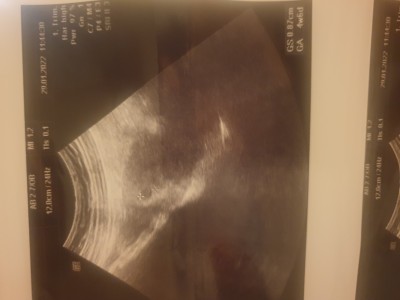

imageultrason goruntum.  yorumlarinizi bekliyorum

Ultrason kağıdında 4 hafta 6 günlük yazıo kese var sanırım doktorun söylemiştir

Ultrasyona göre 4+6 Haftalık hamilesin canım..